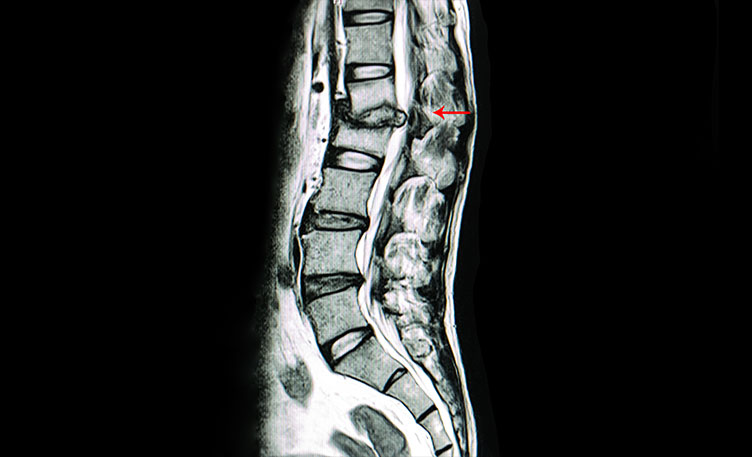

Diagnosis of tuberculosis of the spine is based on clinical examination, imaging studies, and laboratory tests. X-rays or MRI scans can help identify spinal deformities, abscesses, and signs of vertebral destruction. Additionally, a biopsy of the affected area or culture tests can confirm the presence of Mycobacterium tuberculosis bacteria. Blood tests may also be conducted to detect the tuberculosis infection. Early detection is crucial, as delayed diagnosis and treatment can result in irreversible damage to the spine and surrounding tissues.